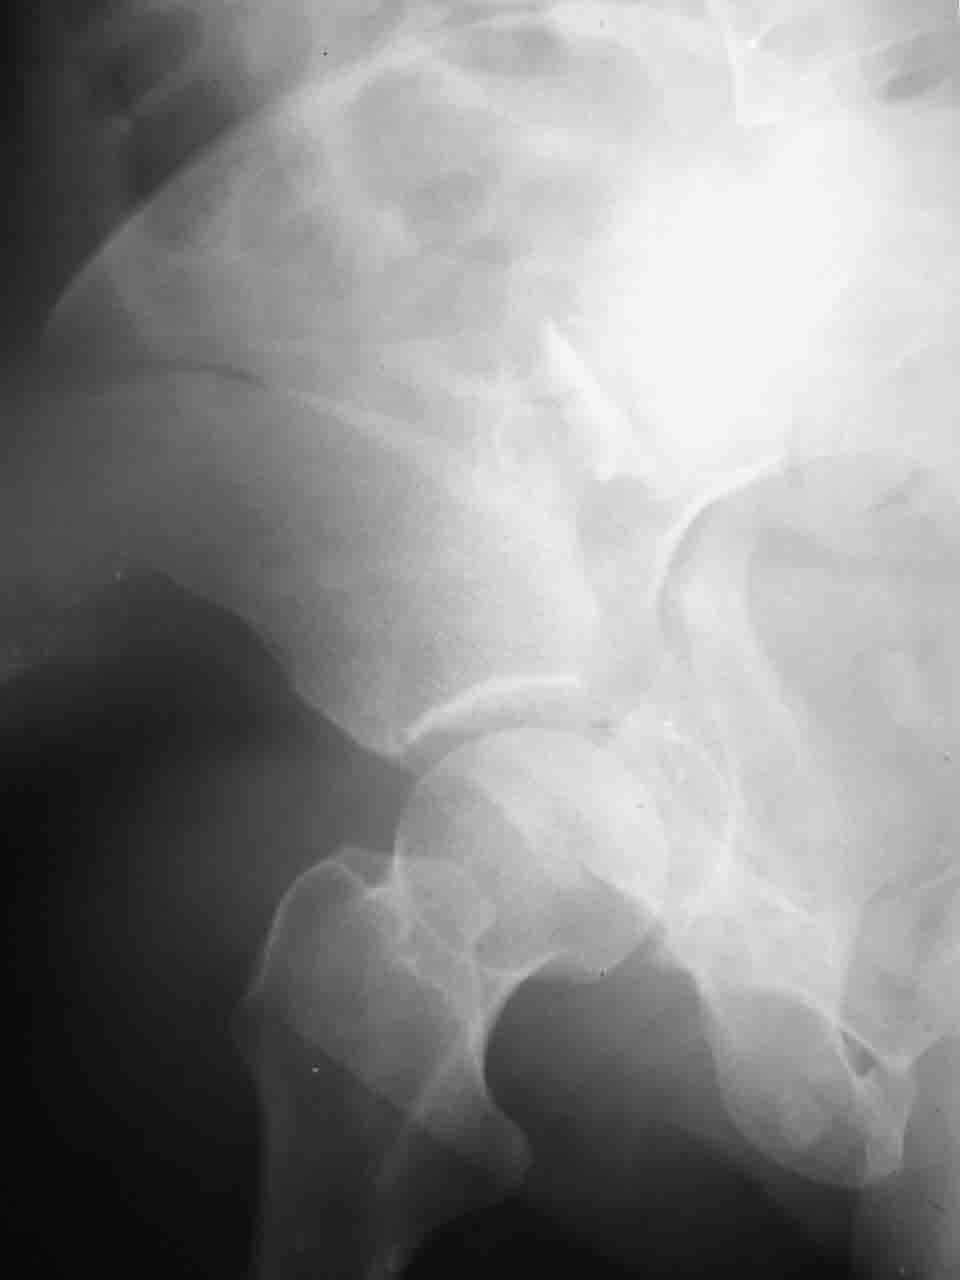

Логика подсказывает, что все-таки лучше иметь анатомически полноценную впадину, хотя ранее упоминалось состояние вторичной конгруэнтности и одно наблюдение у меня есть, когда у больного с полностью нарушенной анатомией впадины и подвывихом головки бедра кзади и кверху боли отсутствовали при относительно достаточном для стиля жизни больного объёме движений. Но это только одно наблюдение и кроме перелома впадины у этогобольного была и тяжелая ЧМТ в анамнезе. Основываясь на формулировке структуры ацетабулюм Э. Летурнеля - как перевернутой буквы Y, впадина для полноценной функции сустава должна иметь сферичность, соответствующую размеру головки бедра и если один из компонентов в дефиците, то функциональные последствия рано или поздно проявятся.

Сложностью, ассоциативностью характера перелома, я бы с радостью воспользовался мининвазивной перкутанной фиксацией винтами, но боюсь, что результат был бы ещё хуже, техникой непрямой репозиции перелома не владею, поэтому пытаясь получить анатомичную впадину приходится широко открывать, по крайней мере пока, а дальше буду пытаться уменьшать пространство...

Илеофеморальный доступ не совсем передний и сравнительно с илеоингвинальным, и Кохера-Лангенбека открывает весь наружный таз кроме самых передних отделов лонных костей, фиксацию которых я не ставил в задачу. Обширность диссекции, большая длительность операции и более высокий риск гетерооссификации - отрицательные моменты в обмен на возможность легче ориентироваться.

Комбинированные доступы - хорошая альтернатива, меньший процент осложнений, но я заметил , что без сбора *мозаики* безымянной кости сложно отрепонировать переднюю колонну, а с нерепонированной передней колонной невозможно анатомично собрать заднюю колонну и соотв. фрагменты стенки - так.что все равно открывать придется широко. Поэтому выбирая комбинированный

подход, передний доступ должен был бы быть продлен до задней трети крыла безымянной кости, а задний - практически до того же уровня, оставляя 6-7 см мостик. При этом вместо одного послеоп. рубца у больного остаются два сравнительно длинных.